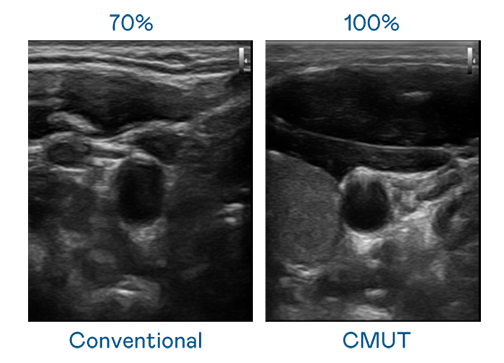

CMUT 技术是一种用电容式微机电元件来产生超音波讯号的技术。与传统 PZT 压电式技术相比,CMUT 频宽增加 30%,更宽频的超音波讯号让影像解析度大幅提升,是实现高影像品质医疗超音波扫描、促进精准医疗发展的关键技术。

超音波影像的解析度高低,首先取决于探头能发出的讯号频宽。JDB电子 CMUT 可提供高清晰的超音波讯号,提供高频宽、高灵敏度、影像纹理细节更高的超音波影像,协助医护人员缩短影像判读时间及利用精准的医疗影像进行诊断。